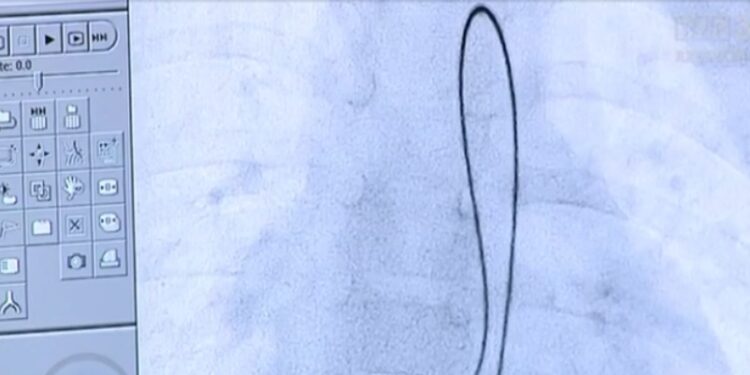

Natomiast Kliniczny Szpital Wojewódzki nr 2 w Rzeszowie pomaga dzieciom z wadami wrodzonymi serca. U trojga dzieci wykonano innowacyjne, małoinwazyjne zabiegi zamknięcia ubytków międzykomorowych. Wada objawia się tym, że brakuje fragmentu przegrody międzykomorowej, dlatego ją uzupełniamy, mówi dr nauk medycznych Oksana Trębacz, kardiolog.

Kliniczny Szpital Wojewódzki nr 2 w Rzeszowie jest jedynym we wschodniej Polsce oraz jednym z nielicznych w Europie ośrodków, w którym leczone są dzieci z ubytkami międzykomorowymi serca.